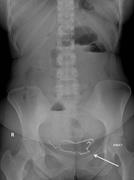

Intraluminal migration of retained surgical sponge as a cause of intestinal obstruction

Basmah A. Rafie and others

Journal of Surgical Case Reports, Volume 2013, Issue 5, May 2013, rjt032, https://doi.org/10.1093/jscr/rjt032